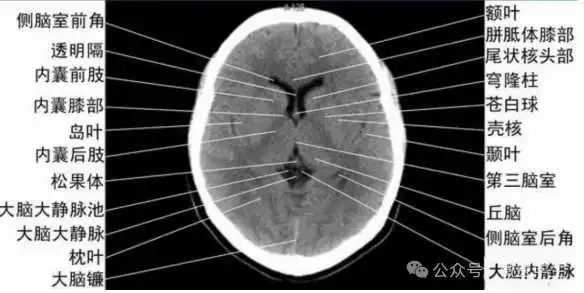

- 内囊前脚(前肢);尾状核和豆状核之间。

- 内囊膝部和后脚(后肢):位于豆状核(由外侧的壳核和内侧的苍白球组成)及丘脑之间。

- 壳核的外侧:外囊、屏状核、最外囊、岛叶(脑岛)。

- 内囊:位于丘脑、尾状核、豆状核之间的白质区,是由上、下行的传导束密集而成。分为三部分:前肢、膝部、后肢。膝部由皮质脑干束;后肢有皮质脊髓束、丘脑皮质束、听辐射和视辐射。

- 外囊:是位于屏状核和豆状核之间的白质带,主要由岛叶发出的皮质被盖纤维组成。